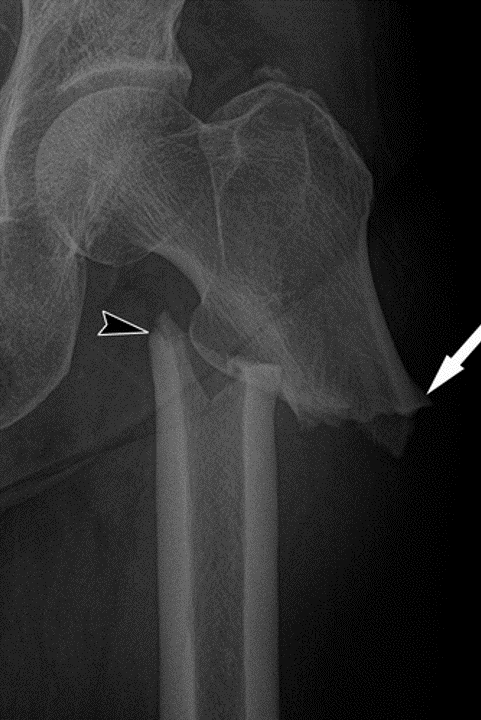

1. Describe the imaging findings.

This is the AP and lateral projection of the index patient’s left hip, showing a spiral/long oblique subtrochanteric femur fracture with mottled appearance proximal and distal to the fracture line.

1. What is your diagnosis?

This is most likely a pathological fracture of the left subtrochanteric femur.